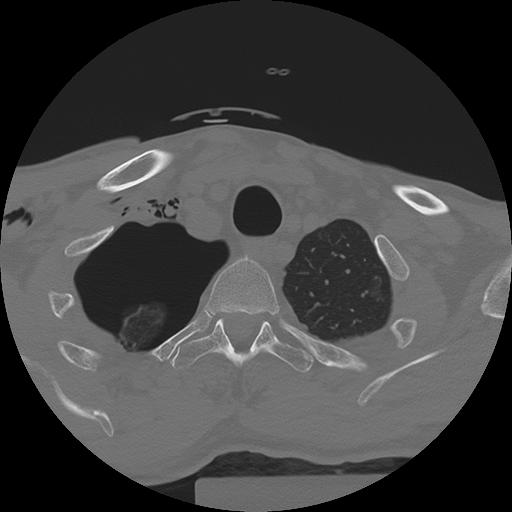

11 HUESO,,Axial,2.0,HUESO,,